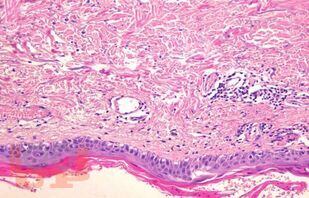

Учебное пособие представляет собой сборник клинических случаев и их разборов, проходивших в клинике факультетской терапии им. С. П. Боткина Военно-медицинской академии на протяжении последних лет. Каждая глава состоит из подробного описания клинического случая, изложения современного теоретического материала, который использовался врачами и преподавателями кафедры в процессе верификации диагноза, определения тактики и оценки результатов лечения.